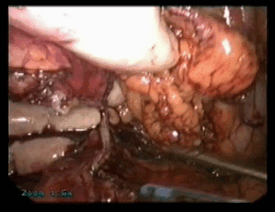

Этапы правосторонней лапароскопической мануально-ассистированной (гибридной) адреналэктомии представлены на серии стоп-кадров из цифрового видеопротокола вмешательства. Рис. …

Рис. 183-184. Создание доступа к правому надпочечнику

Рис. 185-186. Выделение правого надпочечника

Рис. 187-188. Выделение и пересечение аппаратом Liga-Shure медиальной группы сосудов надпочечника